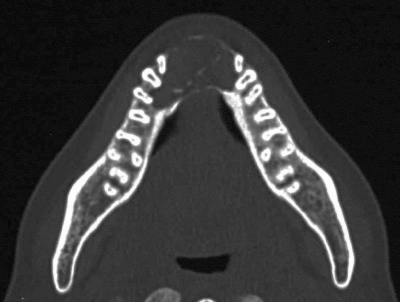

37歳の女性。下顎前歯部の無痛性の腫脹を主訴として来院した。1か月前にかかりつけ歯科医で下顎前歯を抜去されたが、改善しないという。初診時のエックス線写真、CT及び生検時のH-E染色病理組織像を示す。

診断名はどれか。1つ選べ。